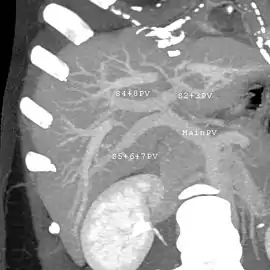

Maximum intensity projection (MIP) CT image as viewed anteriorly showing the anomalous hepatic veins coursing on the anterior surface of the liver

Lateral MIP view in the same patient as previous image

With the recent advances of noninvasive imaging, living liver donors usually have to undergo imaging examinations for liver anatomy to decide if the anatomy is feasible for donation. The evaluation is usually performed by multidetector row computed tomography (MDCT) and magnetic resonance imaging (MRI). MDCT is good in vascular anatomy and volumetry. MRI is used for biliary tree anatomy. Donors with very unusual vascular anatomy, which makes them unsuitable for donation, could be screened out to avoid unnecessary operations.

MDCT image. Arterial anatomy contraindicated for liver donation

MDCT image. Portal venous anatomy contraindicated for liver donation